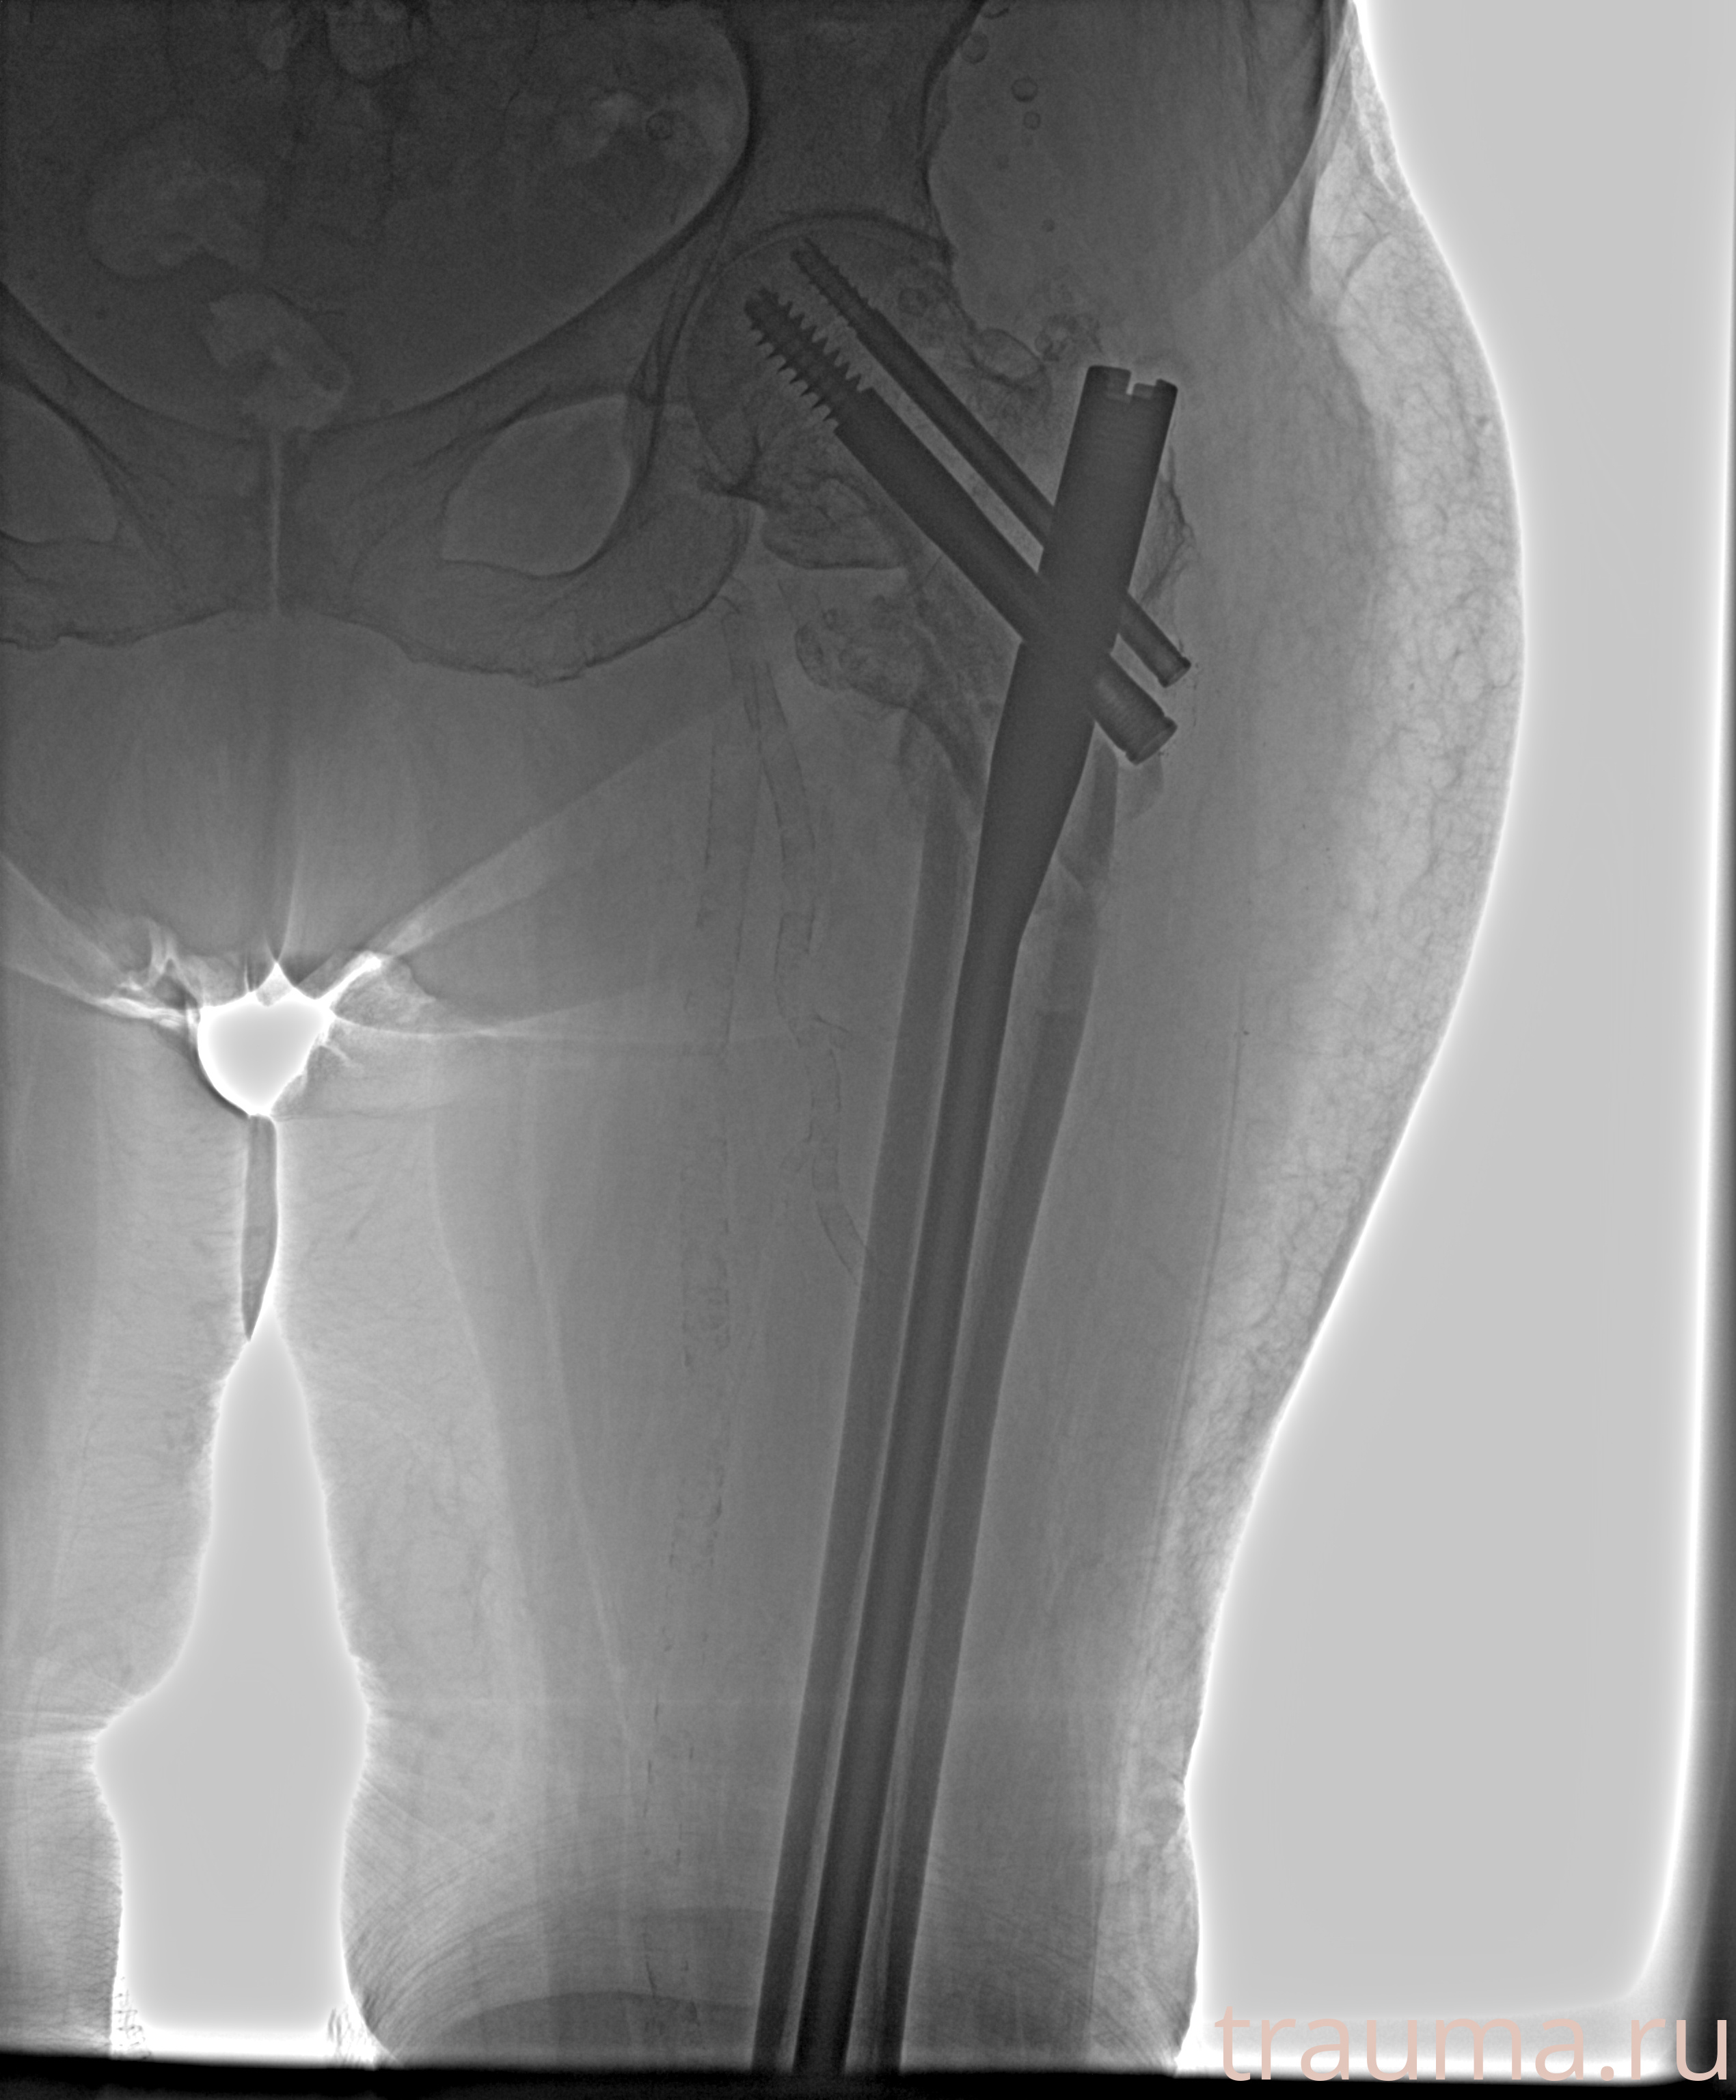

Рентгенограммы

Рентген на дому: по вашему адресу приезжает врач-рентгенолог, травматолог-ортопед с мобильным рентгеновским аппаратом, проводит диагностику травмы или заболевания, делает необходимые рентгенограммы, дает рекомендации по дальнейшему лечению. Получить качественные снимки в домашних условиях возможно благодаря уникальной методике, разработанной МосРентген Центром для института  Склифосовского